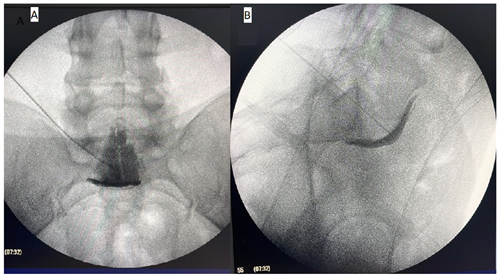

Este estudio tiene como objetivo mostrar los resultados del bloqueo del plexo hipogástrico superior (Figura 2) para el manejo del dolor pélvico crónico. Se reporta la reducción significativa del dolor (menos del 50 % de EVA inicial) solo en el 45 % de los pacientes al primer mes, y en el 36 % y 23 % a los meses 3 y 6, respectivamente. A su vez, el porcentaje de mejoría promedio de EVA al primer mes fue de 37,3 %, de 30 % al tercer mes y del 20 % al sexto mes. Nuestro estudio difiere de los resultados encontrados por otros autores (9,10,11), quienes han reportado mayor efectividad del bloqueo para dolor pélvico crónico, pero dichas diferencias pueden deberse a la población intervenida, con diferentes características, como por ejemplo la etiología oncológica, técnicas diferentes (uso de guía tomográfica) y finalmente a diferentes operadores.

Fig. 2. Imagen fluoroscópica del bloqueo hipogástrico superior. A: vista anteroposterior, medio de contraste en línea media. B: vista lateral, medio de contraste anterior a espacio L5S1 y al promontorio sacro.